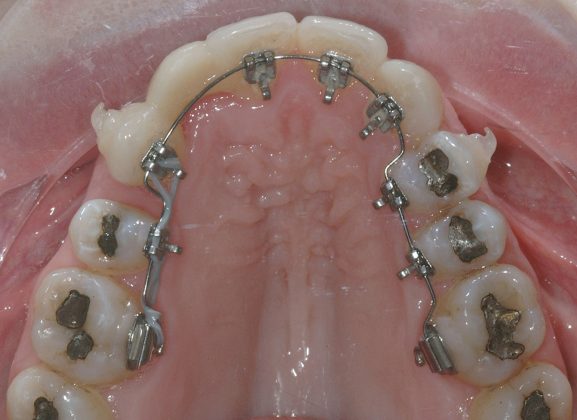

Per formulare corretta diagnosi e piano di cura, lo studio del caso ha previsto la raccolta di documentazione completa standard, ovvero fotografie del viso e intraorali (Figure 1a-e), radiografia panoramica e teleradiografia del cranio in proiezione laterale (Figure 2a-b) per la relativa analisi cefalometrica e modelli di studio.

Il protocollo terapeutico ha previsto l’estrazione del primo premolare inferiore sinistro (3.4) e del primo superiore destro (1.4), l’applicazione di una apparecchiatura fissa linguale 2D e di una meccanica asimmetrica di ancoraggio e movimento ortodontico a entrambe le arcate (Figure 3a-b).

Il trattamento è iniziato con l’estrazione dei due premolari in unica seduta in anestesia locale e l’applicazione simultanea, dopo una settimana, della apparecchiatura linguale inferiore e superiore, non essendoci problemi di overbite e potenziali interferenze in occlusione tra l’apparecchiatura superiore e i frontali inferiori. All’arcata superiore è stata effettuata una iniziale chiusura dello spazio estrattivo con forze molto leggere in ancoraggio medio su arco .014” Nichel-Titanio e successivamente .016” Nichel-Titanio, bondato in prima fase per maggior stabilità direttamente sulla superficie mesiale di 2.4.

Nota tecnica: il movimento iniziale di distalizzazione della corona di 1.3 mediante tipping distale (vista la posizione radicolare iniziale) è stato ottenuto con una catenella elastica leggera inserita su 1.6, 1.5 e ancorata su 1.3, abbracciando per maggior controllo l’aletta disto-occlusale e quella gengivale del bracket linguale.